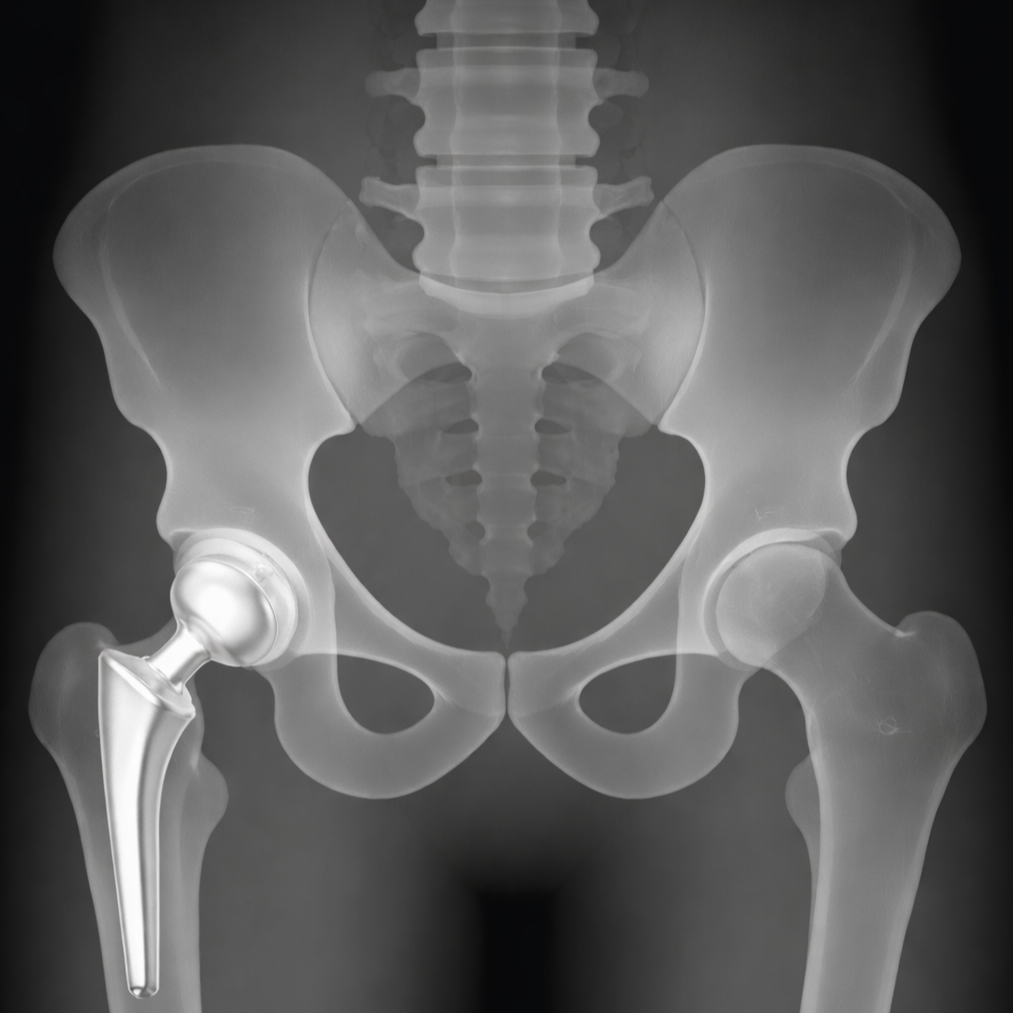

Gianluca Coccioli

ortopedico a Milano